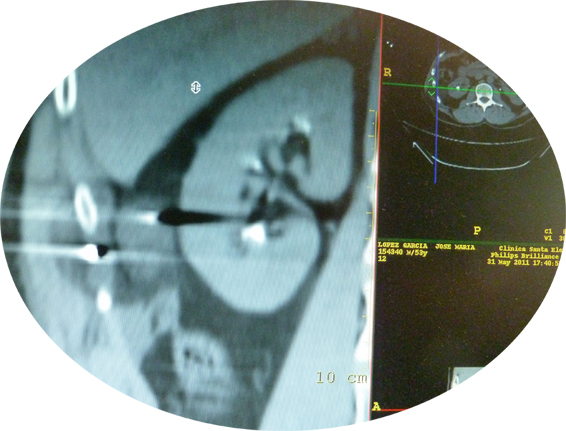

-Cáncer de Riñón mediante TAC y ecografía conducida